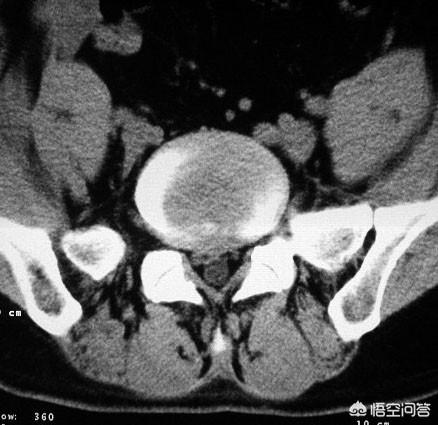

绝大多数腰椎间盘突出症,都好发于L4-5和L5-S1椎间盘,L3-4相对少的多,其他椎间盘造成症状的更少,这就造成多数腰椎间盘突出症的人,出现下肢疼痛多数在腿的外侧或者腿的后侧,腿外侧是L4-5椎间盘突出症,腿后侧是L5-S1椎间盘突出症。

腰椎间盘突出症有一个特点,那就是L1-2椎间盘突出压迫的是L2神经,L2-3压迫的是L3神经,以此类推,L4-5椎间盘突出压迫的是L5神经,由于L5神经主要行走于腿的外侧,因此,这个椎间盘突出的人多数是腿外侧症状,L5-S1也是这样。